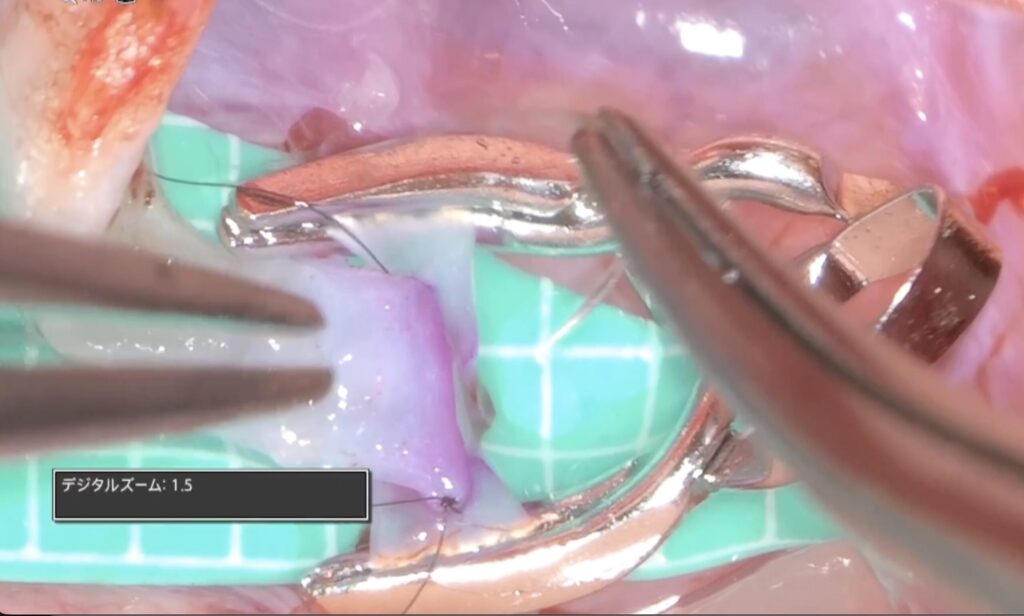

外視鏡を用いると吻合時にはデジタルズームをフットスイッチで入れると瞬時に高拡大にできます。

糸が通ったら、また瞬時にデジタルズームを切ります。

そして糸を結びます

次の針はまち針のように通してあり、しかも糸は常に繋がっていますので、針は無くなりません(Needle parking mehtod)